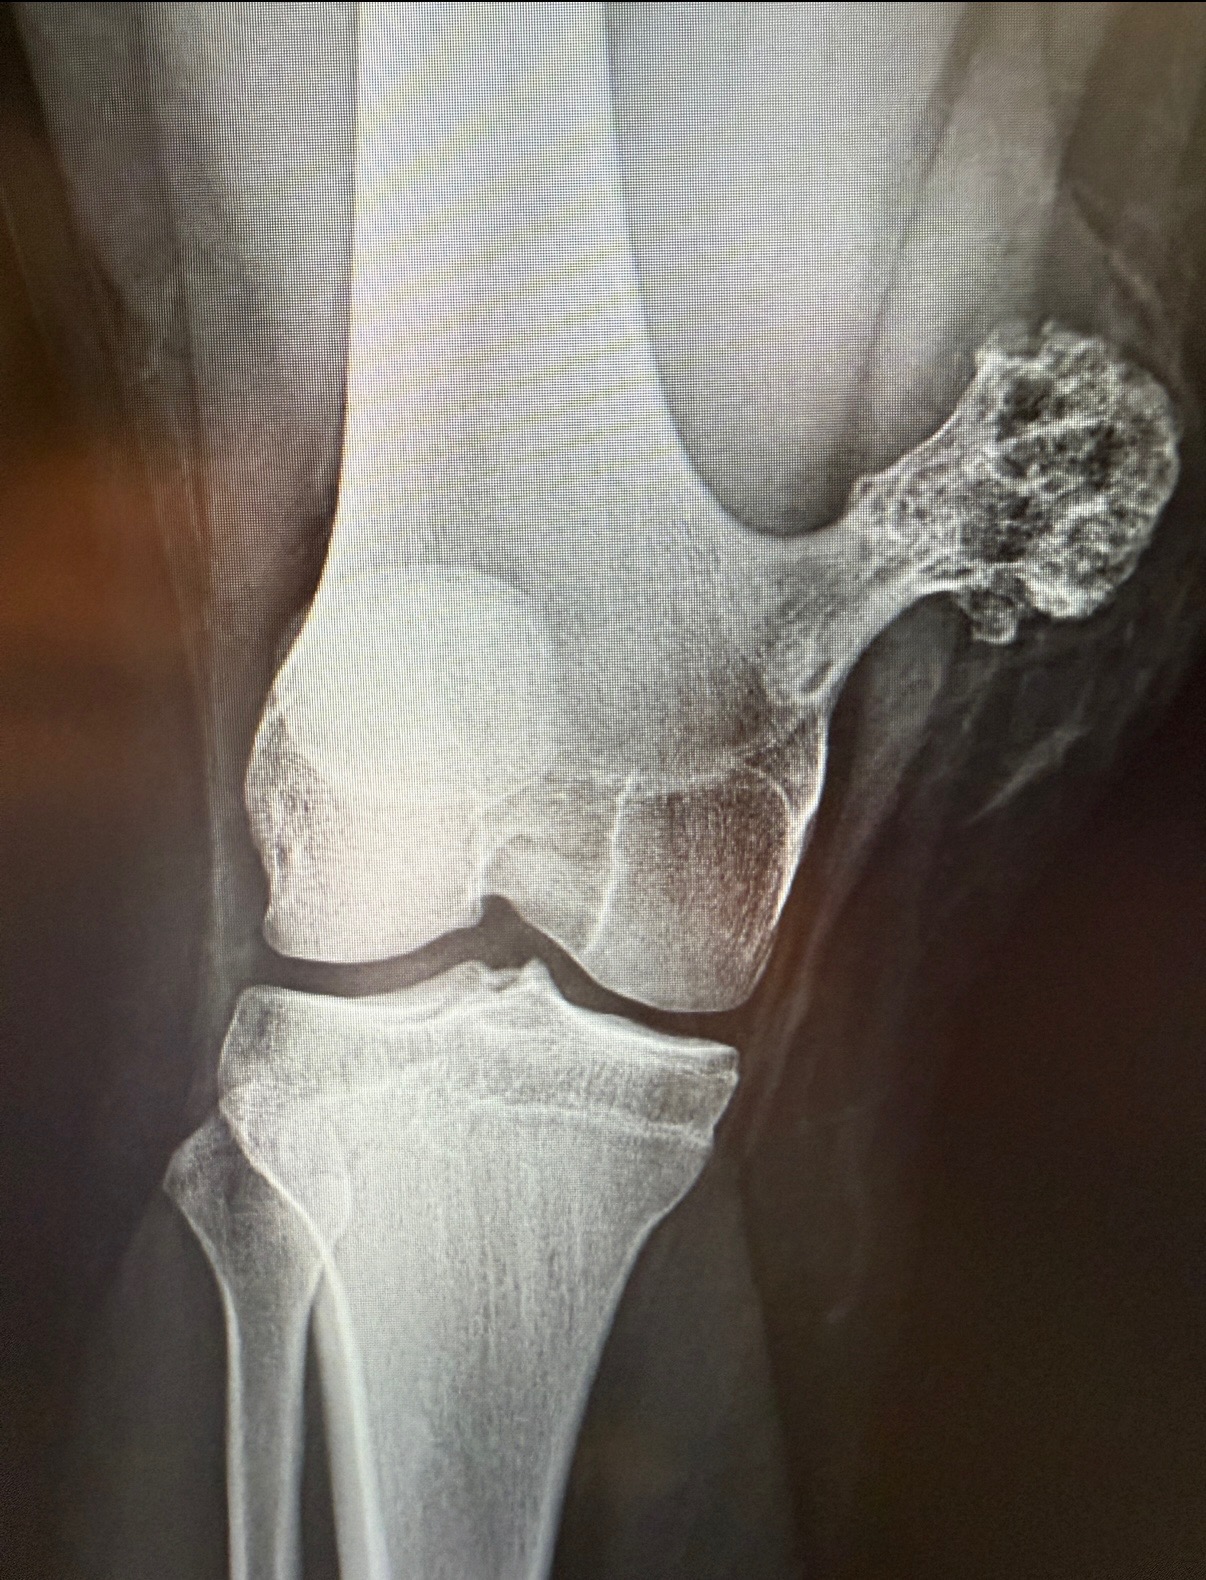

HAGS Clothing started during a moment when everything in my life slowed down at once. I already knew I had a tumor in my leg, but while playing soccer with my friends at Mizzou, I fractured the golf ball–sized tumor and also had my patellar tendon repaired due to ongoing issues from Osgood-Schlatter. I had to come home from Mizzou for two weeks for surgery, then return to school knowing I would be on crutches for a couple more weeks.